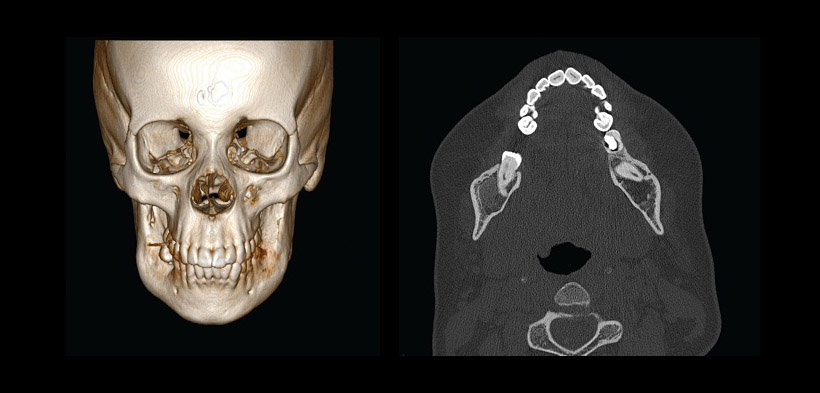

Fig. 1 Radiografía panorámica de una paciente femenina de 18 años, que muestra el crecimiento bilateral de la lesión en el cuerpo, rama, y las apófisis coronoides de la mandíbula, produce la erupción atípica de los terceros molares inferiores, y la reabsorción de la raíz distal del primer molar inferior izquierdo.

Fig. 3 Radiografía panorámica del paciente anterior posterior a la cirugía y a la administración de calcitonina, se observa la formación y la sustitución de la lesión por tejido óseo neoformado.